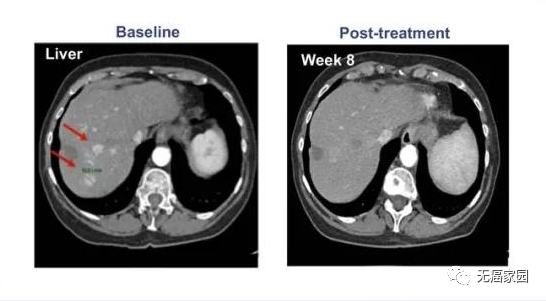

典型病例1

01、04号患者 53岁 男性

来源 CARsgen Therapeutics

晚期胃癌伴肝、肺、骨转移和多发淋巴结和腹膜转移,已接受包括 PD-1 抗体在内的2种全身治疗,CLDN18.2 60%(3+),接受CAR-T治疗后,肿瘤缩小近50%,持续缓解32周。